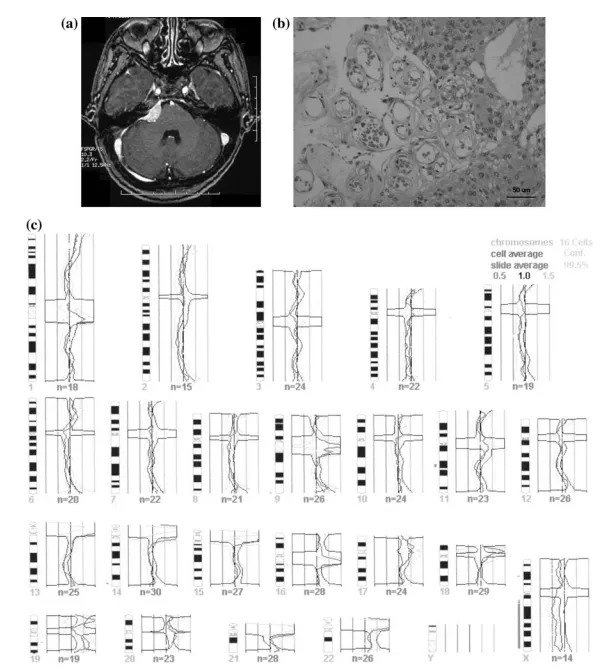

一位48岁女性患者因左耳听力丧失及眩晕症状就诊于当地医院。磁共振成像检查显示左侧桥小脑角区存在占位性病变(图1a)。实施开颅手术后,术中发现肿瘤侵犯梅克尔腔及内听道,并向鞍上区延伸。在完整保留所有神经功能的前提下实现肿瘤全切。组织学检查显示肿瘤细胞呈小叶状排列,卵圆形细胞核偶见中心空晕,可见大量血管瘤样成分(图1b),病理确诊为脑膜上皮型脑膜瘤。标本NF2检测呈阳性反应,Ki-67指数与p53阳性率分别为1.0%和0.2%。按照文献方法进行CGH分析显示染色体拷贝数异常为Xq缺失(图1c)。术后6年随访MRI检查未见肿瘤复发。

图1a:钆增强T1加权磁共振图像,显示左侧桥小脑角区均匀强化病灶

图1b:病例1标本显微照片(苏木精-伊红染色,×40),显示伴有血管瘤样成分的脑膜上皮型脑膜瘤

图1c:病例1各染色体比较基因组杂交结果图谱。染色体编号标注于对应模式图下方,深色线表示荧光强度比均值,浅色线表示标准差(n为采集数据的中期分裂象数量)。染色体模式图左侧线段表示相对缺失区域,右侧线段表示相对增益区域